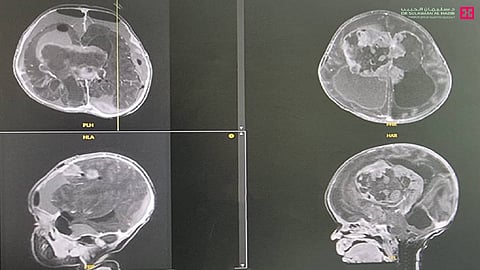

الذي قال أن الطفلة عمرها "15" يوم، وأسعفت إلى المستشفى وهي بحالة صحية معقدة، وتعاني إشكالات في عمليتي التنفس والبلع، بالإضافة إلى اضطراب وتسارع بنبضات القلب، فتم نقلها إلى العناية المركزة مباشرة بسبب حالتها الصحية العامة، ومن ثم خضعت لفحوصات دقيقة، كالتصوير المقطعي المحوسب SCAN - CT والرنين المغناطيسي MRI، وأظهرت النتائج وجود ورم ضخم في الغرفة الثالثة من الدماغ وضاغط على مركز التنفس ومركز القلب.

وتابع د. مسعود قائلاً أن الفريق الطبي أخضع الحالة لنقاش مستفيض مع استشاري طب الأطفال، وتم الوصول إلى خطة علاجية متكاملة، وأجريت للمراجعة عملية عاجلة استغرقت "5" ساعات، وتم فيها استئصال الورم بدقة متناهية، مع المحافظة على الدم وتقليل النزف إلى الحد الأدنى، وتم استخدام مجموعة من التقنيات الحديثة كالميكروسكوب الحديث، ومراقبة الأعصاب والسونار، وتكللت في النهاية بالنجاح التام، ونقلت الطفلة إلى العناية المركزة لحديثي الولادة، وتم وضعها على جهاز التنفس الاصطناعي لمدة "3" أيام، قبل أن يتم تحريرها ونقلها إلى غرفة التنويم، حيث بقيت قيد الرعاية الصحية الحثيثة لمدة "7" أيام تحسنت خلالها حالتها الصحية، وغادرت بعدها المستشفى، ولاحقاً أظهرت فحوصات ما بعد العملية، استئصال كامل الورم مع المحافظة على الأعضاء الحساسة المجاورة لها من أعصاب ومراكز تحكم، إضافة إلى أن الفريق الطبي حافظ على مستوى الدم رغم استمرار العملية لأكثر من "4" ساعات، وذلك بالعمل المستمر على تقليل النزيف، حيث أن كمية الدم بالنسبة للأطفال بعمر أسبوعين لا تزيد عن "150" ملم وفقدان الكثير منه يعني وضع حياتهم على المحك.